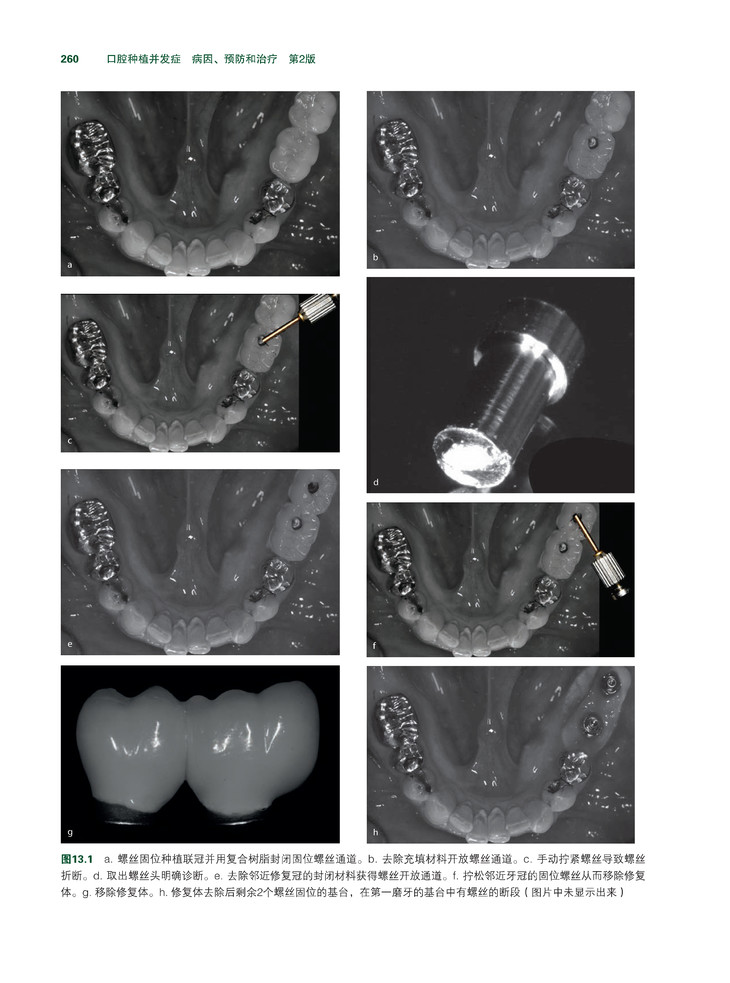

牙种植已成为最常用和发展最快的代替缺失牙的修复技术。虽然种植牙以可预期性、良好的功能和耐用性赢得患者和医生的青睐,但其并发症可能发生在从患者评估到维护治疗的任何阶段。

《牙种植并发症:病因、预防和治疗》是第一本基于循证研究、为各个层次的临床医生提供全面临床知识的参考书。本书选取了口腔临床与种植牙相关的各专业各具特点的典型病例,既包含了最常见的种植牙并发症,也包含了罕见但独特的种植牙并发症。 本书在内容的编排上结构清晰,包括牙种植的诊断,牙种植的治疗计划,以及种植体放置、修复、和维护治疗,牙种植等各个时期的并发症等。此外,与骨增量和上颌窦提升相关的并发症也给予了详细的讨论,尤其是其病因和预防。本书的每一章都力求做到了言简意明、层次清晰,每章最后都有“重点提示”总结该章的基本要点。除临床知识外,本书还为读者提供了种植牙领域的最新工业标准,并探讨了与种植牙相关的医学法律问题。书的最后以一组由该领域的专家提供的典型病例作总结,展示了与种植牙相关的复杂并发症及其多方面的治疗措施。